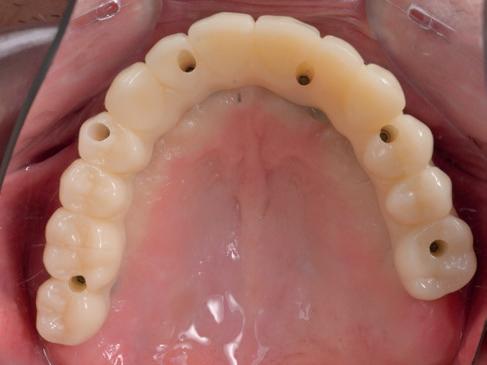

Plaatsen vaste brug

De technicus leverde op basis van de tijdelijke brug, de vast brug op implantaten af. Deze is van volledig zirkoonoxide met een titanium frame aan de binnenzijde voor de stevigheid (afbeelding 16-18). Een volledige brug van alléén zirkoonoxide is namelijk fractuur gevoelig. Na verwijderen van de tijdelijke brug kon de mondhygiëne van de patiënt gecontroleerd worden bij de implantaten. Patiënt hield het netjes schoon met een elektrische tandenborstel en een waterpik. Het is van belang dat de brug zonder spanning op zijn plek geduwd kan worden en deze niet kan kantelen op de abutments. Na het plaatsen van de brug werden de schroefjes getorqued op 15 Ncm, waarna de esthetiek, occlusie en articulatie gecontroleerd konden worden.

Daarna werden de schroefgaten gevuld met Blue M gel, teflon tape en composiet (afbeelding 19 en 20). Patiënt was zich zeer tevreden met het functionele en esthetische eindresultaat (afbeelding 19 en 20). Er was ook een nette hoektand en frontgeleiding. Voor de fonetiek werd een filmpje opgenomen, de F en de S werden netjes uitgesproken (afbeelding 21). De patiënt vervolgt zijn parodontale nazorg bij de mond-

hygiënist waarbij ook de mondhygiëne bij de brug wordt gecontroleerd. Op de OPT na 2 jaar (afbeelding 22) is het botniveau rondom de implantaten stabiel en is patiënt tevreden met zijn vaste brug.